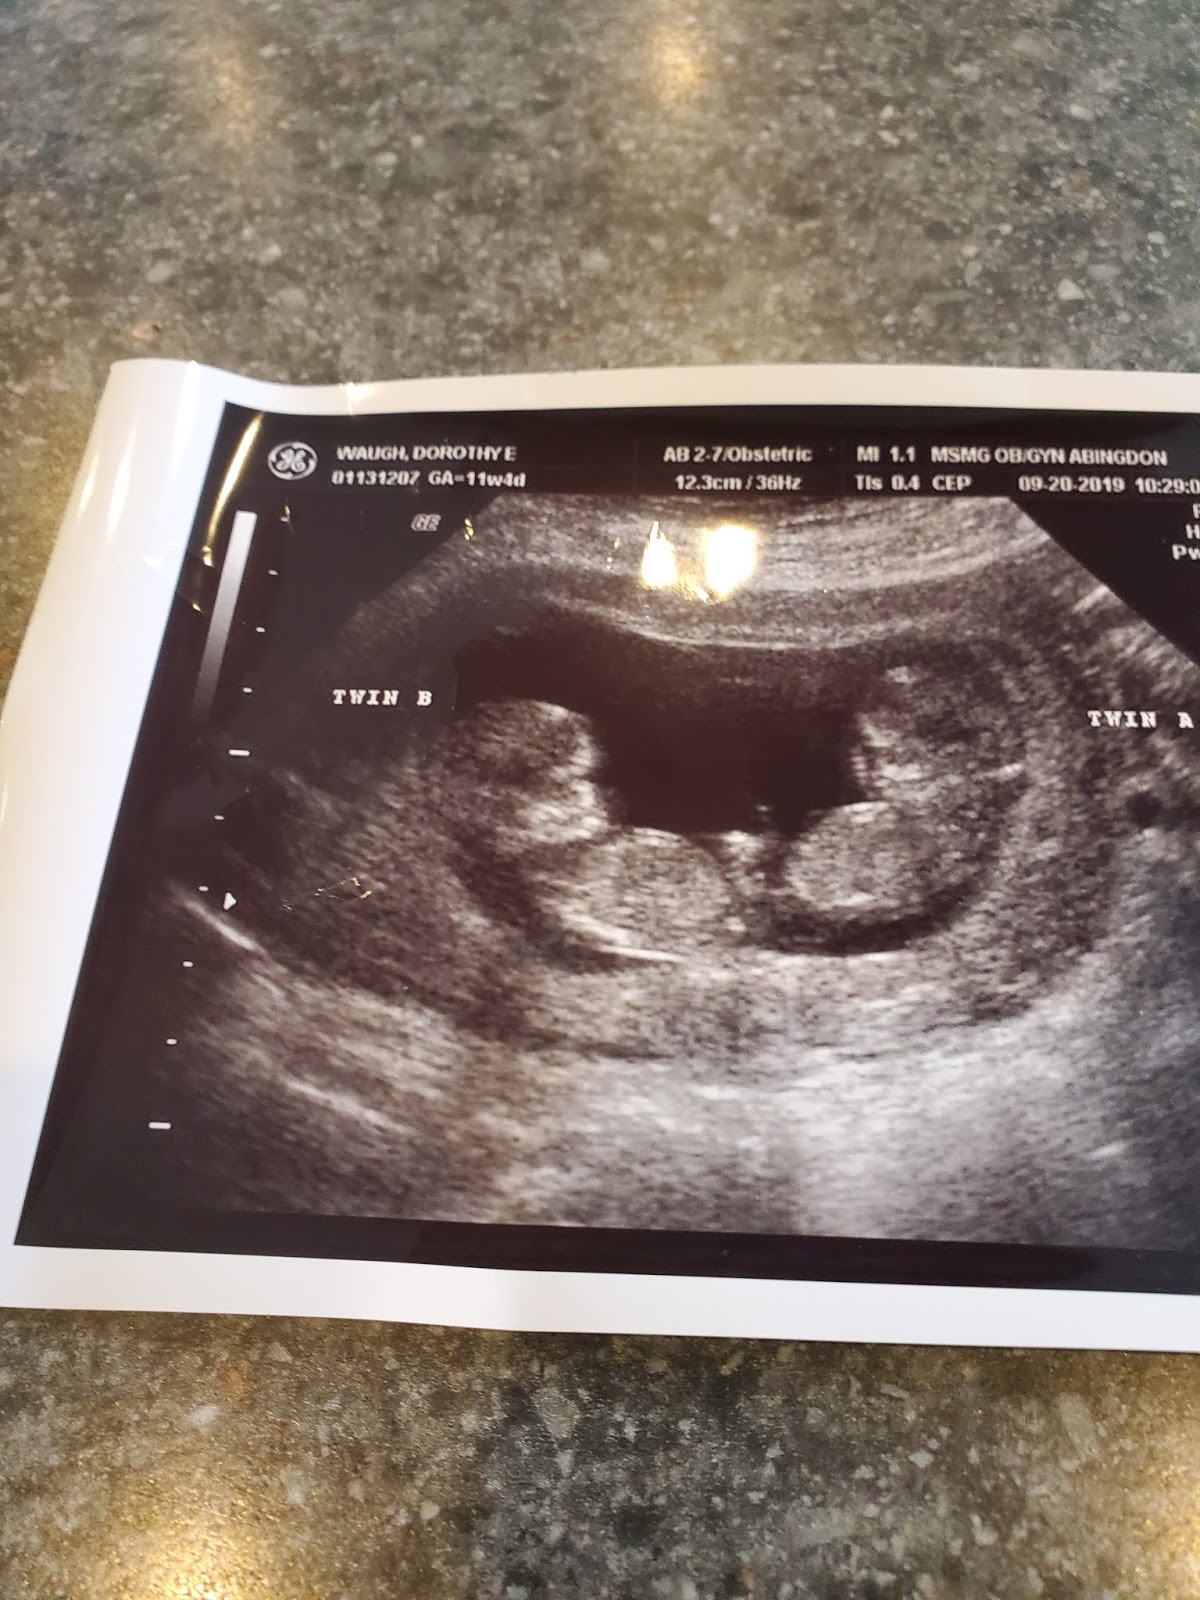

Later that evening, youngest daughter, called. She is expecting identical twin boys in April. She and her husband along with their son, Blake, who will be two in January wanted to come down. They had been to her doctor appointment, and they wanted to eat dinner with me. Since she is having twins, the twins are in the same placenta but in different sacs, she sees a specialist every other week.

Before dinner, she explained to me that both boys are doing great...they are growing and are the same size and she will return in two weeks. After dinner, she showed me the pic of the ultrasound and told me they had decided on names. Twin A 's name is Aiden Charles (after my dear Charlie) and Twin B's name is Liam Grant (Liam comes from William and William was my father's name who passed away shortly after I got married with cancer). The tears flowed again well, more like heavy, heavy tears. I love the names. She said she had thought about her dad all day and I told her I had to. She was sad that he won't be here to see them, But I told her that Charlie hand picked them in Heaven and sent them to her and Kenneth. And just like I tell Blake about his Buddy (Charlie was called Buddy not Papaw) I will make sure these two boys will know what a special person their Buddy was.